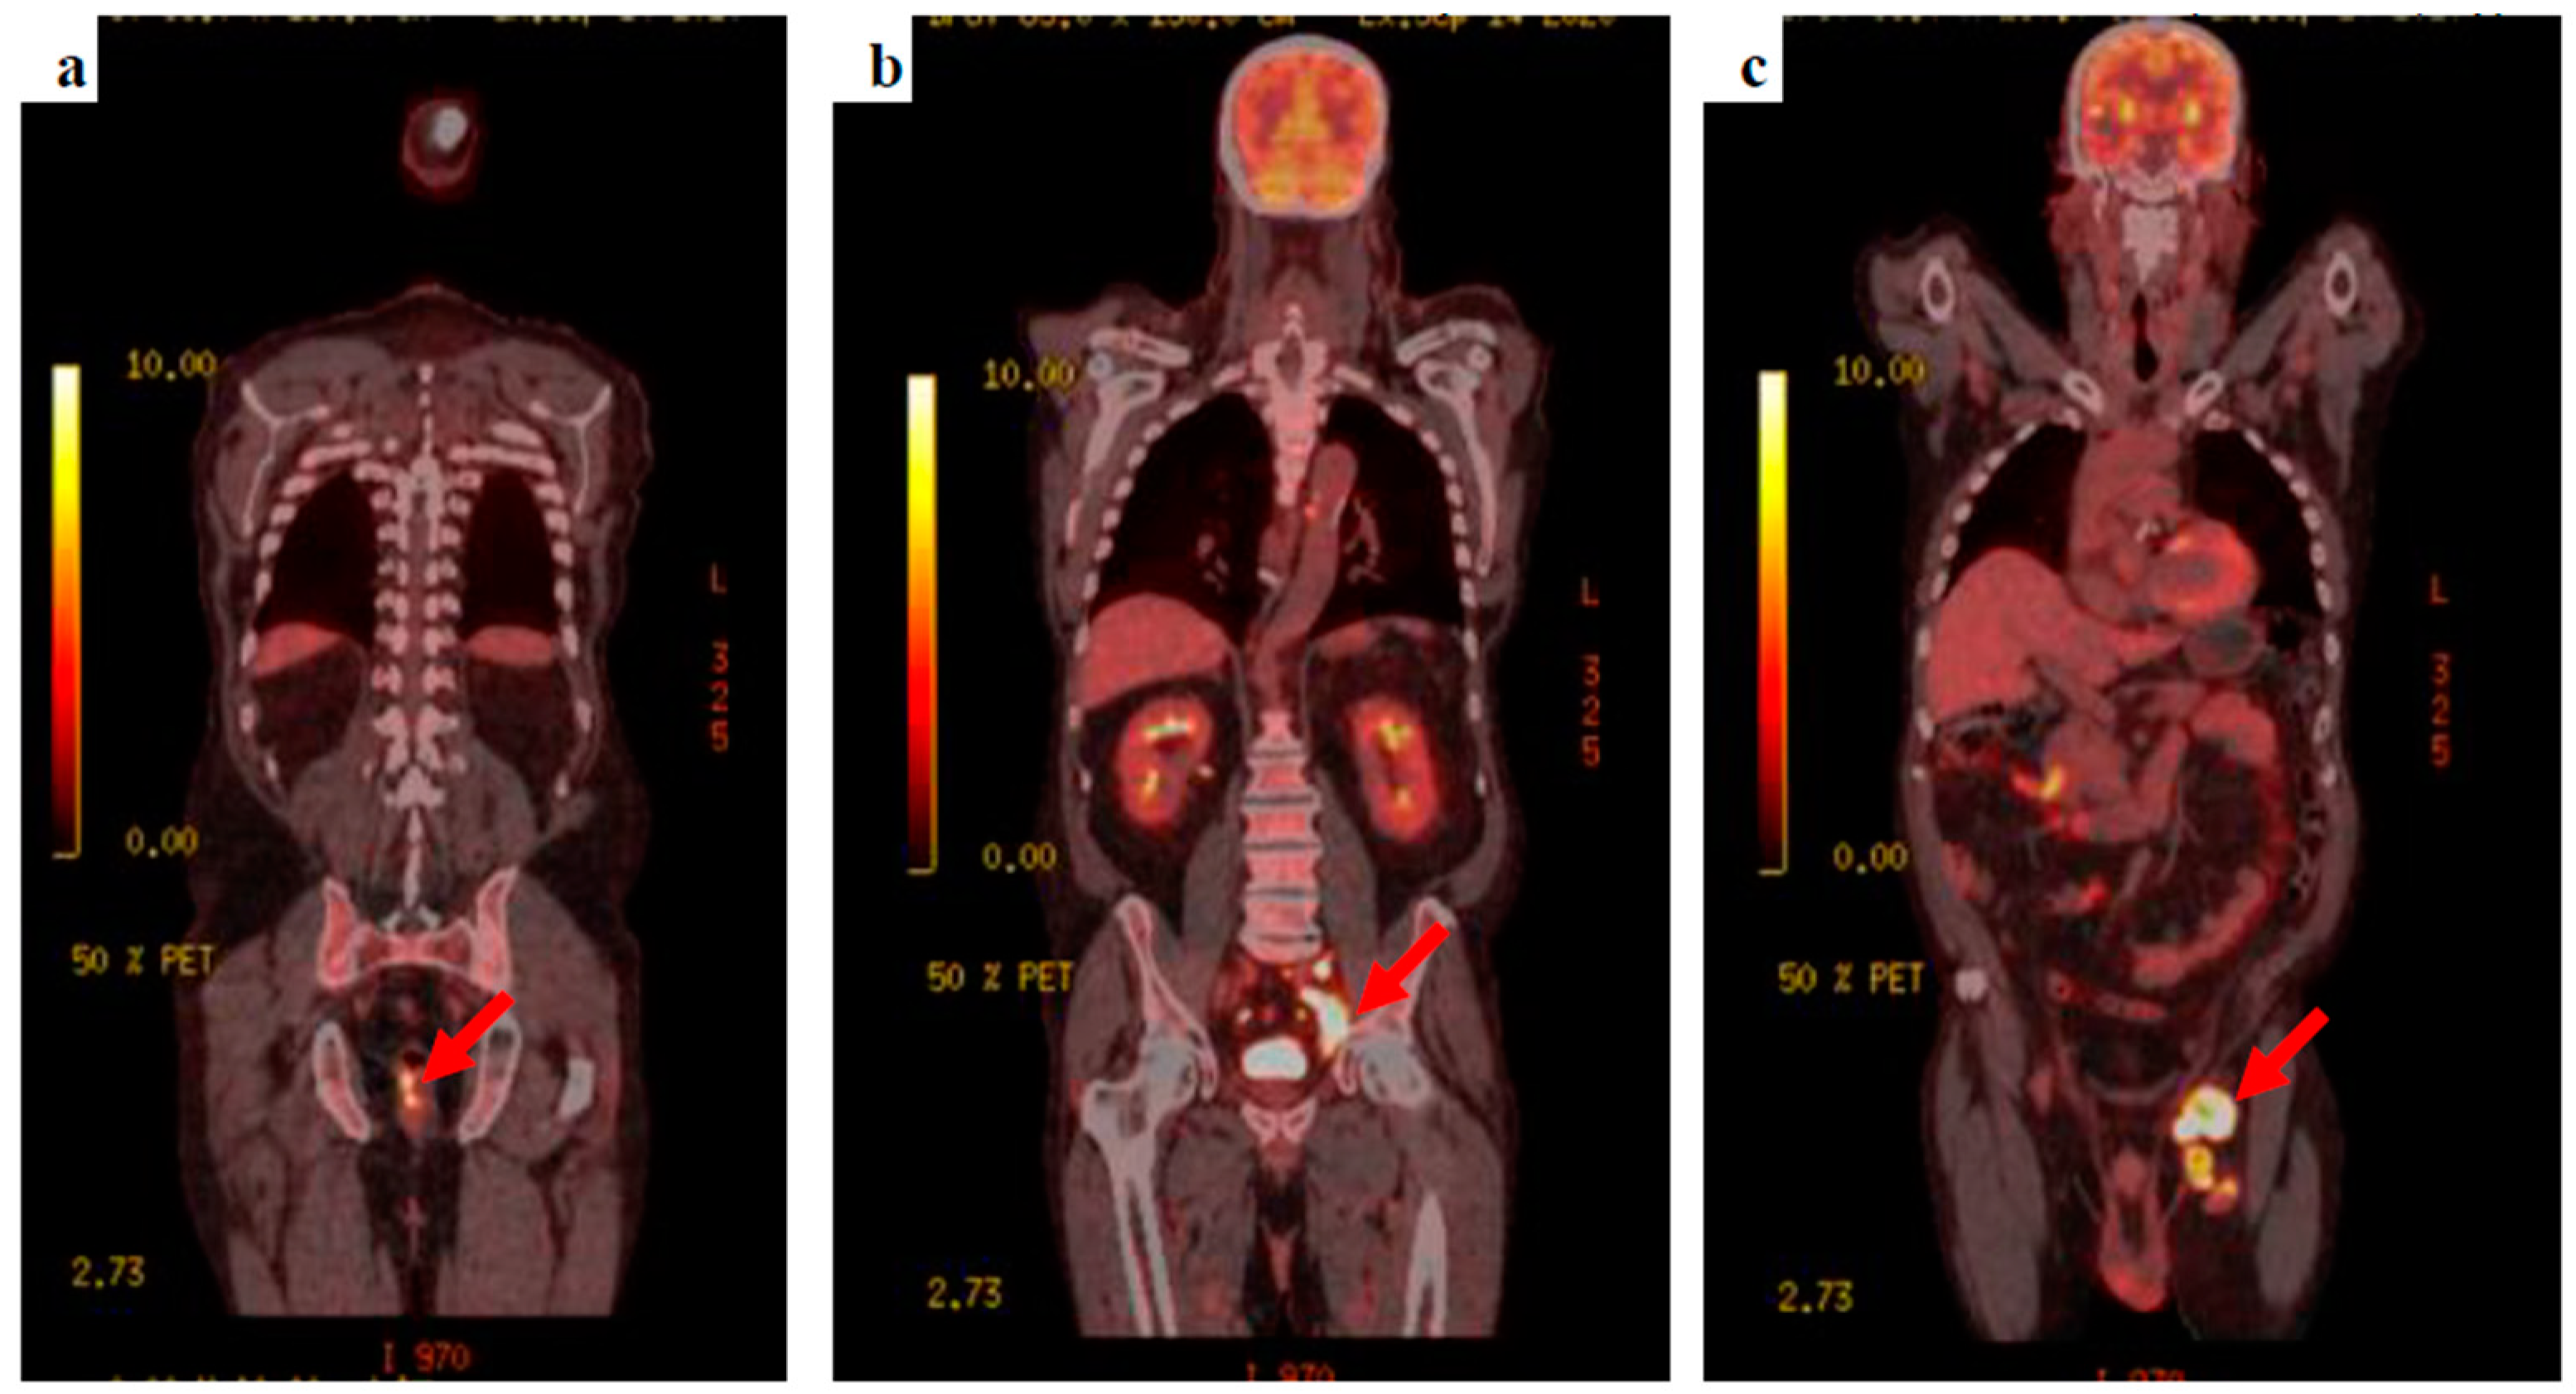

The patient’s clinical condition improved and he was keen to go home, agreeing to be referred to the neuro-oncology multidisciplinary team meeting. Whole-body fluorodeoxyglucose (FDG)-positron emission tomography (PET) was requested to find the primary tumour, showing extensive FDG-avid lymph nodes within the left groin, the left external iliac station, extending into the left common iliac group with retroperitoneal lymphadenopathy extending into the posterior mediastinum. A focus of FDG avid uptake was seen at the 6–9 o’clock position close to the anorectal junction (Figure 3).

Figure 3.

18F-FDG PET-CT images (a) the anorectal primary lesion with SUVmax 12.2, (b) deep, left external and common iliac nodal uptake, and (c) bulky, extensive, left inguinal lymphadenopathy.

Tumour markers were unremarkable (prostate specific antigen (PSA) = 1.0 µg/L and carcinoembryonic antigen (CEA) = 3.2 µg/L). A primary anorectal malignancy with extensive FDG avid nodal metastatic spread was suspected. Following discussion at the lower gastrointestinal multidisciplinary team meeting, a percutaneous ultrasound-guided core biopsy of the left groin node was requested.

This patient presented with seizures and the brain MRI findings were consistent with metastatic malignancy. There was no evidence of cutaneous melanoma primarily noted on clinical examination, and the CT-CAP was not able to demonstrate the primary, highlighting some of the limitations of standard imaging techniques. FDG PET findings raised the suspicion of colorectal origin at the anorectal junction and the patient was referred to the colorectal multidisciplinary team meeting based on the most common aetiology for that location and pattern of spread, causing delay in addressing the melanoma primary, with the conclusive diagnosis later revealed by biopsy. This again illustrates the limitations of imaging alone in this condition, and the key role of histology and, particularly, immunohistochemistry, given that a substantial proportion of ARMMs have an amelanotic appearance even microscopically [14].